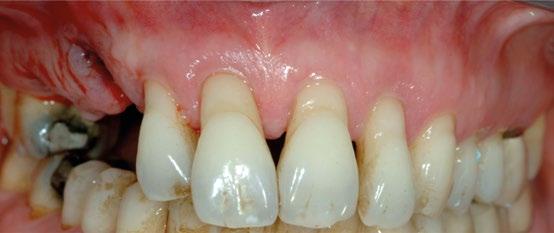

Paciente mujer de 35 años, con amplia exposición gingival en sonrisa y alta demanda estética (Fig. 1, 2).

Su solicitud inicial es volver a blanquear el 21, que había sido previamente endodonciado y había recibido sucesivos tratamientos blanqueadores que habían recidivado. Refiere ligera molestia en la papila interincisiva. En la exploración radiográfica intraoral 1 2

11

caso clínico IMPLANTOLOGÍA

se aprecia una extensa reabsorción radicular interna, con el consiguiente defecto óseo, que se confirma con un CBCT (Fig. 3, 4, 5). Se informa a la paciente del riesgo de fractura espontanea. Esta solicita solucionar el problema antes de que avance más.